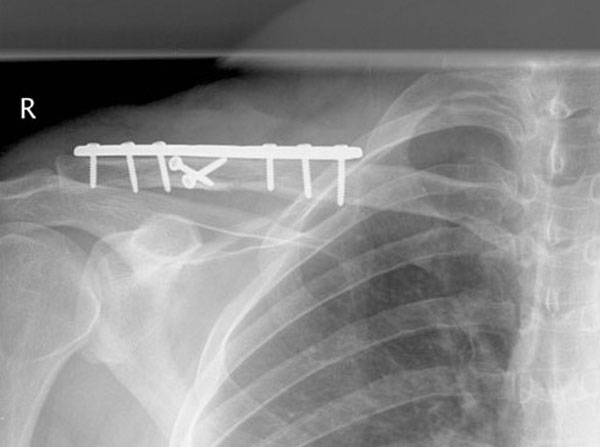

This man is 38 years old and originally fractured his clavicle when much younger. It was left to heal naturally but unfortunately healed in a poor position. He fell while playing soccer and fractured through the previous mal-union and callus. He had surgery and within just six weeks was almost healed and had a good range of motion, function and strength.

Malunion fracture before surgery

Malunion fracture after surgery

Move the slider to compare before surgery and 6 weeks after surgery